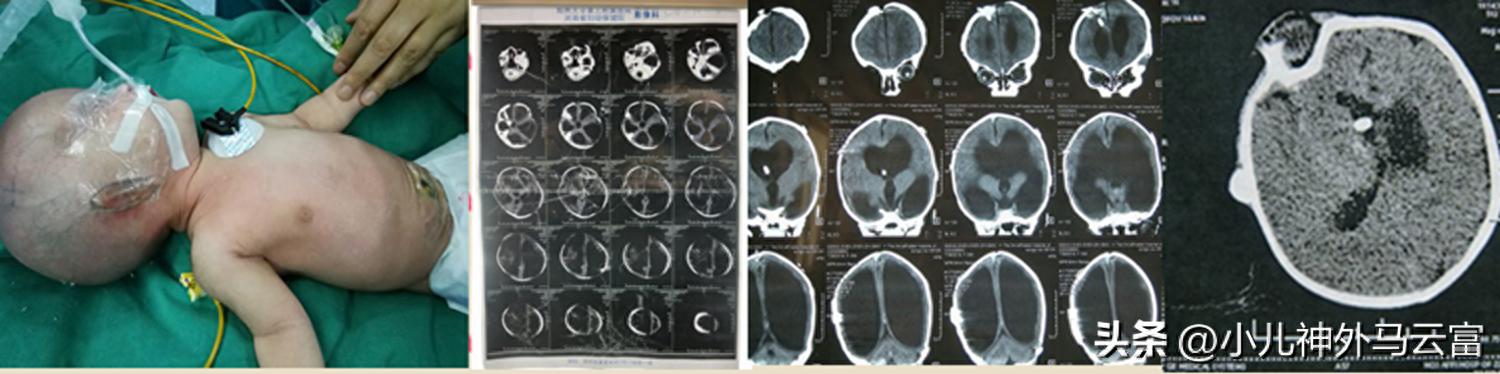

嬰幼兒腦積水主要由於一:感染,宮內感染、各種病毒、梅毒、螺旋體感染性腦膜炎等等,未能及時的控制,所導致的。二:出血,顱內出血後引起的纖維增生,剷傷顱內出血吸收不良。三:腫瘤,可阻塞腦脊液循環的任何一部分,較多見於第四腦室附近或脈絡叢乳頭狀瘤。四:某些遺傳代謝疾病,圍產期及新生兒期窒息嚴重的維生素A缺乏,都可以出現,胎兒先天性腦積水多導致死胎,出生以後,腦積水可能喫現在任何的年齡,多數於生後六個月就出現了,年齡小的小朋友可能會伴有骨縫未結合,頭顱容易擴大,顱內壓增高的症狀比較少,當頭圍進行性的增大的時候,而且成爲圓形額不前突,前囟擴大特別的明顯,會出現雞蛋殼敲擊的感覺,甚至像乒乓球的一種破壺的聲音,落日淚等這樣的表現,嚴重的影響到肢體以及智力的發育,必須需要進行手術治療,但是手術也會存在一定的風險。

腦積水確實有一定的發病率,很多家屬都很關心孩子的預後的情況,而且很擔憂,其實我們可以通過一些知識瞭解下腦積水。

腦積水肯定是一種顱腦的病變,預後有些是不可評估的,包括孩子的智力,身體功能各方面的發育,是需要等患兒大一些才能評估出來的。

對一些比較輕的,而且孩子顱腦發育都是比較良好的腦積水來說,經過手術處理,術後恢復都是不錯的。而且在臨牀上,我們接觸過很多患兒術後大概一到兩歲以後都是比較聰明的,而且身體發育條件都特別好,然後基本來說和正常孩子一樣的。

所以腦積水並不是不可治,而且術後恢復也是比較好的。但極個別的孩子,情況就比較糟糕,早期沒有引起注意,腦積水引起嚴重的創傷,這種情況下術後恢復會比較差,甚至是會出現身體發育阻滯,就是持續癲癇等發生。